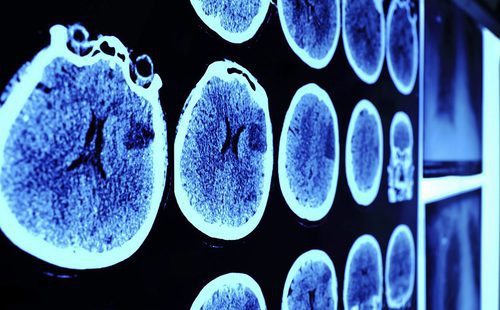

Por otro lado si el aneurisma se da en la zona del cerebro es mucho más complicado de detectar por qué no presenta síntomas visibles. La única manera de detectar un aneurisma cerebral seria realizando alguna prueba médica como por ejemplo puede ser una resonancia magnética de nuestro cerebro. En este caso lo único que podemos detectar es un fuerte dolor de cabeza que suele confundirse con migrañas con cefalea.